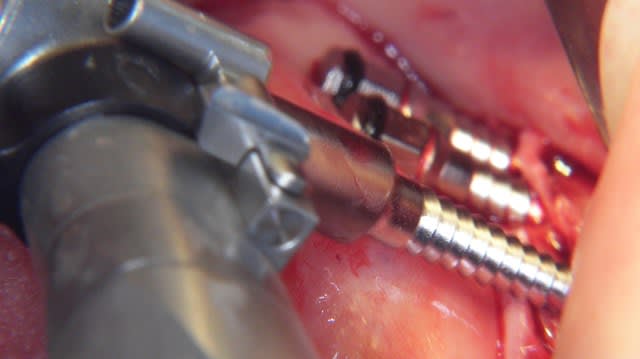

Un exemple de splitting sectoriel au maxillaire sup avec :

- piezo,

- osteotome,

- implant Astra osseospeed,

- comblement par mélange os autogène et BioOss,

- recouvrement par membrane BioGide + conjonctif palatin.

La suite dans quelques mois. ;-))

Très juste Dumaille. Le lambeau est d'épaisseur totale d'une part au niveau des incisions crestales verticales et sur toute leur hauteur et d'autre part jusqu'á la moitié de la hauteur du volet osseux. Le reste est en épaisseur partielle. Point important. Merci de l'avoir souligné.